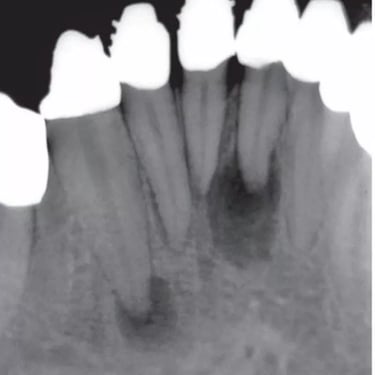

Absceso Periapical Agudo

Un absceso periapical agudo es una acumulación de pus en la punta de la raíz del diente debido a una infección.

Los pacientes suelen experimentar dolor intenso, hinchazón y fiebre.

Esta condición requiere tratamiento inmediato, como el drenaje del absceso y un tratamiento de conducto. Sin tratamiento, la infección puede propagarse a otras áreas.